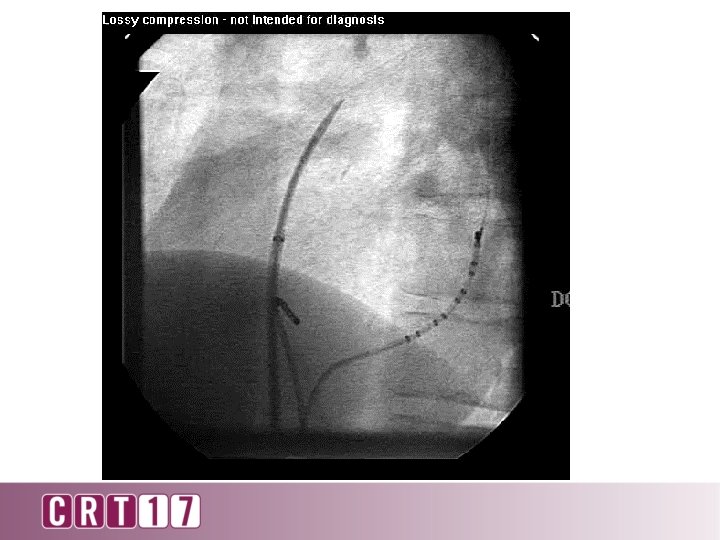

2 cm 20 degree RAO